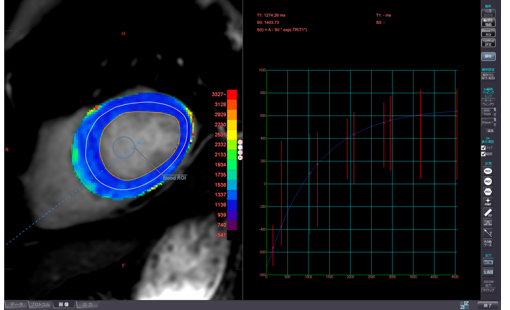

左心室機能解析:心臓の機能解析が可能です。

非造影心臓MRI

T1 mapping:左心室の性状評価が可能です。